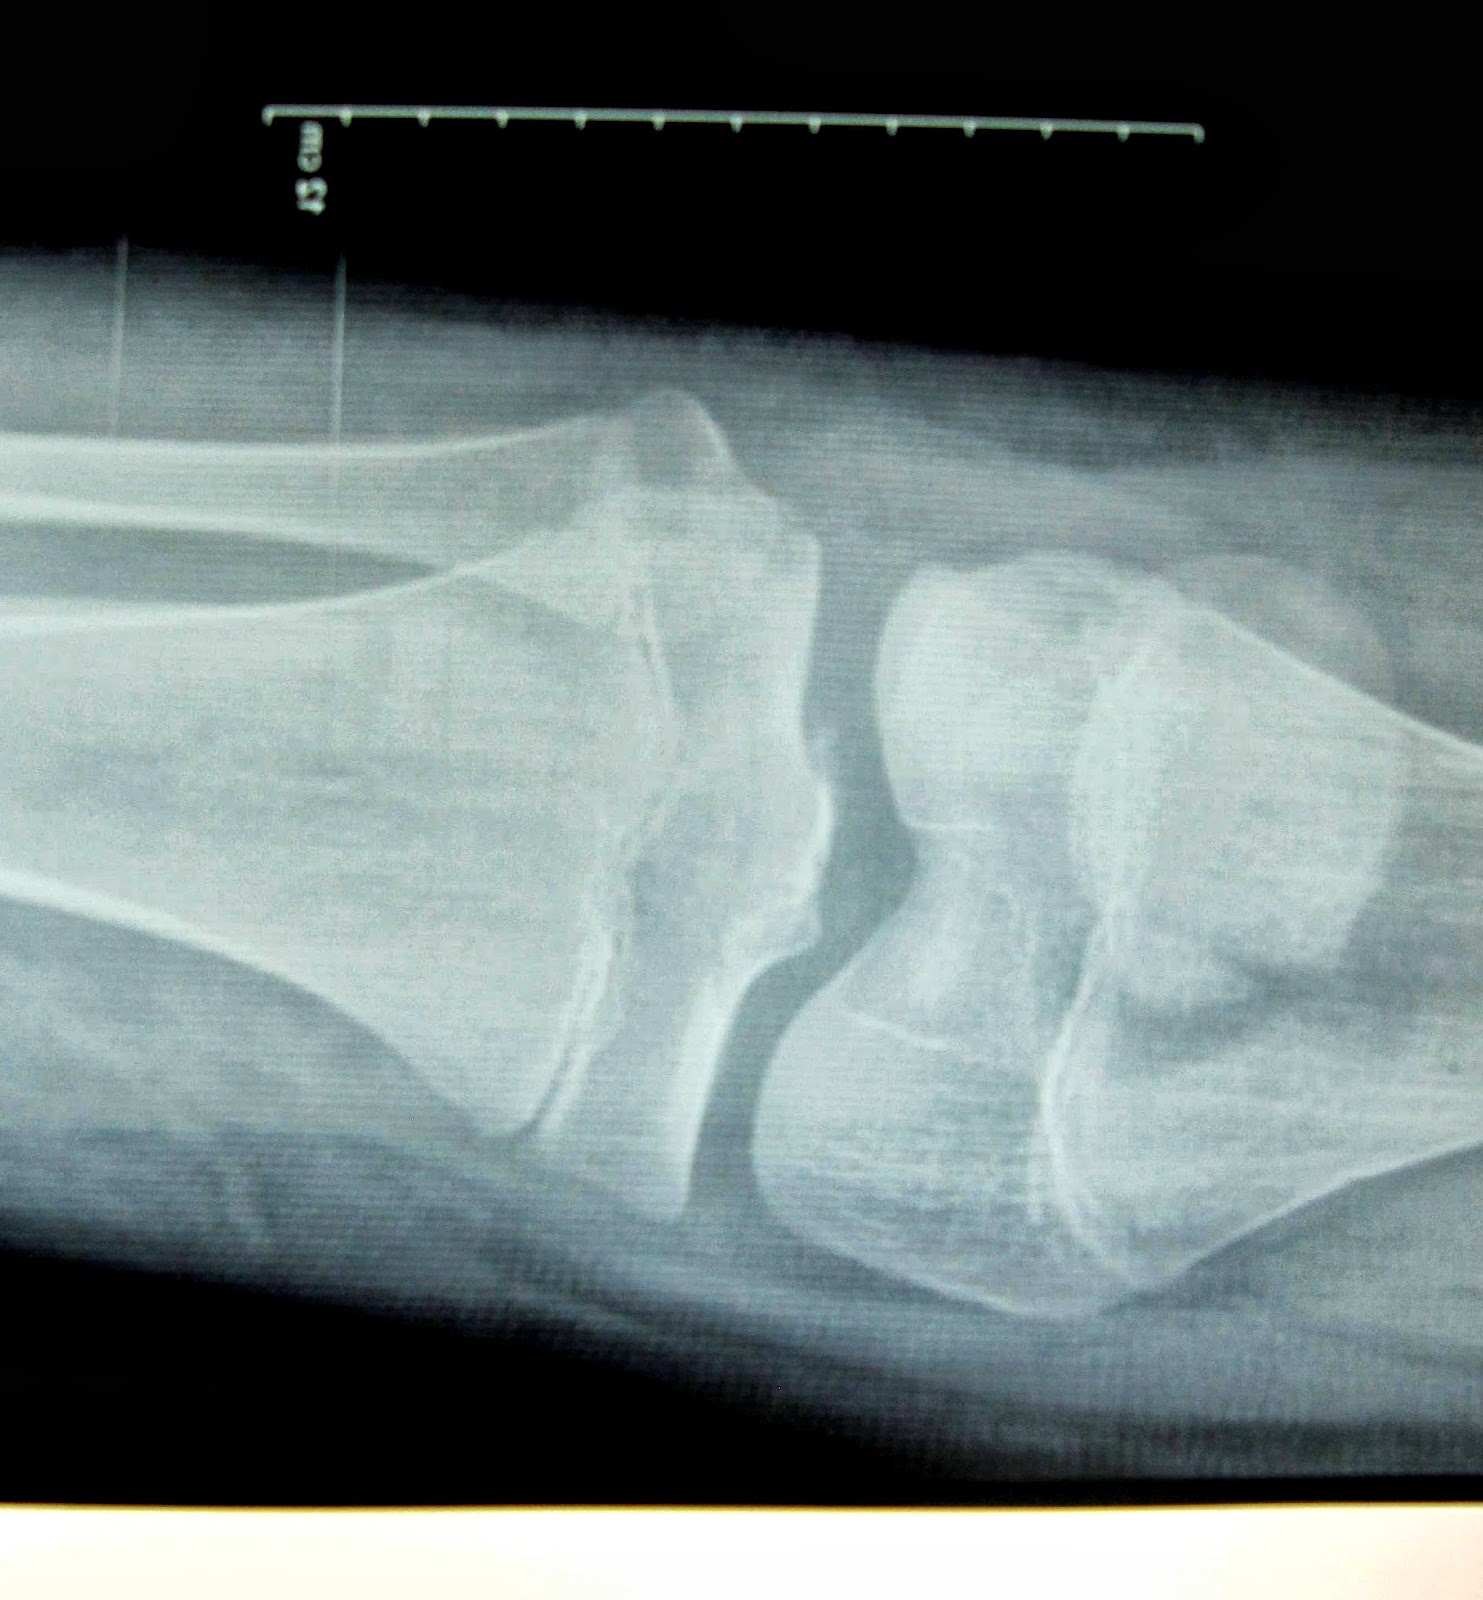

| X QUANG TRƯỚC PT: DẬP NÁT XƯƠNG ĐẦU NGÓN 2, 3. | ||

| NGÓN 3 ĐẦU XƯƠNG DI LỆCH NẰM PHÍA DƯỚI |

| X QUANG TRƯỚC PT LẠI: NGÓN 3 ĐẦU XƯƠNG BỊ XOAY |

| SAU PT LẠI: XƯƠNG GÃY HẾT BỊ XOAY |

| SAU PT LẠI: KHÓ NHÌN THẤY GÃY XƯƠNG ĐẦU NGÓN 3 |

Đây là trường hợp bệnh nhân nữ, 19 tuổi bị gãy kín 1/3 dưới thân 2 xương cẳng chân trái, kèm gãy mắt cá ngoài. Chiều ngày 8/10/2013, bệnh viện TP. Pleiku, tỉnh Gia lai đã tiến hành phẫu thuật cho bệnh nhân. Cuộc phẫu thuật kéo dài 2 giờ với kỹ thuật đinh nội tủy có chốt cho xương chày, kim Kirschner cho xương mác, cố định cả mắt cá ngoài bằng kim Kirschner và vis xốp. Đặc biệt đây là phẫu thuật kín dưới C-arm và trong đó có những kỹ thuật biến đổi. Ngay trong lúc mổ đã cho thấy một kết quả thật hoàn hảo như mong đợi.

| XQ TRƯỚC MỔ |

| XQ SAU MỔ |